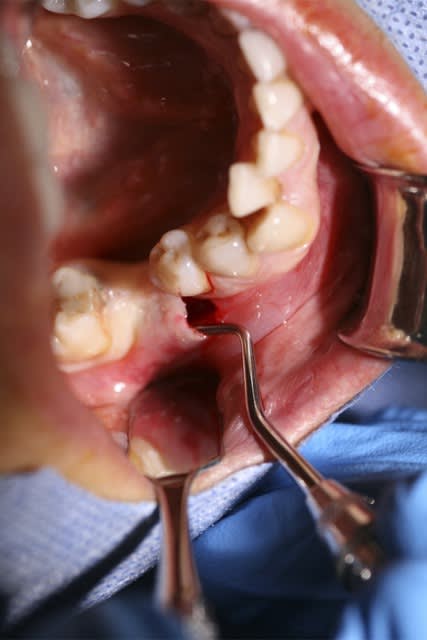

image 12 et 13: réouverture, forage et pose des implants ( les implants ont été posés par le DR A. L dans le 31)

image1 réouverture et dépose du matériel ( du tissu fibreux s'est insinué dans les fentes mésiales et distales que j'ai du cureter)

image2 pose d'une membrane pour faire une ROG sur ces dites fentes

image 3 réentrée à 3 mois

image4 pose des implants + re ROG autogène)

image 5 vis de cicat ( re 2mois )

image6 visualisation de la cicat gingivale 6 semaines après la pose des vis de cicat.

désolé pour les photos merdiques et je n'ai pas de photos de la prothèse.

Voilà tant du point de vue osseux que gingival, cette technique ne me convient pas parfaitement.